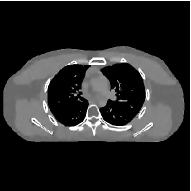

III-B3 Generalization Capability Comparisons between a “Denoising” Deep NN and the Proposed PWLS-ST- Method

This section compares the generalization capabilities between the proposed MBIR method, PWLS-ST-, and a denoising deep NN, FBPConvNet [14], that are trained from the phantom data; in particular, we tested the trained PWLS-ST- and FBPConvNet models to phantom and clinical scan data. The results in Fig. 6 show that the non-MBIR FBPConvNet method has higher overfitting risks, compared to the proposed PWLS-ST- MBIR method. When tested on clinical scan data, PWLS-ST- achieves much more accurate reconstruction, compared to FBPConvNet. See Fig. 6(b). When tested on phantom data, FBPConvNet generates more unnatural features as the number of views reduces, although it gives lower RMSE values compared to PWLS-ST-. See zoom-ins in Fig. 6(a). The FBPConvNet results above correspond to those in the recent work [16] that FBPConvNet [14] generated some unexpected structures.